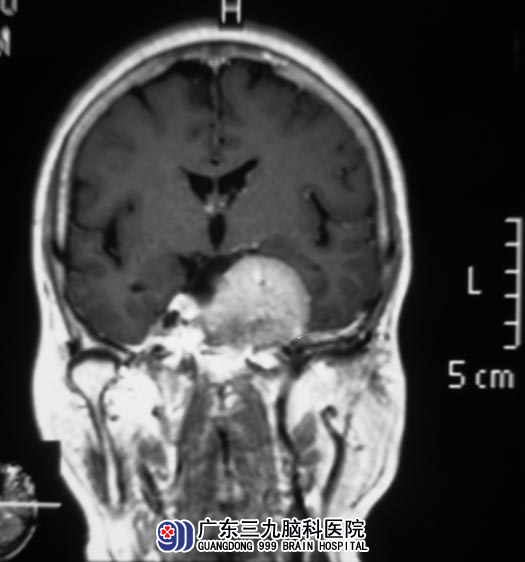

广东三九脑科医院MR检查提示:左侧岩斜区示一不规则形实质性占位性病变,大小约为46.2mm×33.5mm×34.0mm,病变向上生长挤压视交叉,侵犯左侧海绵窦,并突破鞍隔长入鞍内。综合神经外科 鲁明主任初步考虑为脑膜瘤。

完善相关检查后,鲁明主任主刀,在全麻下行左侧岩斜区、海绵窦脑膜瘤切除术,术中沿颅底游离并分离肿瘤,见肿瘤质韧,粉红色,血供丰富,主要位于小脑幕,并长入海绵窦内,包绕左侧颈内动脉及滑车神经,与三叉神经、动眼神经关系密切,在显微镜下将肿瘤顺利切除。术后陆姨未再诉头痛。病理结果为:过渡细胞型脑膜瘤。